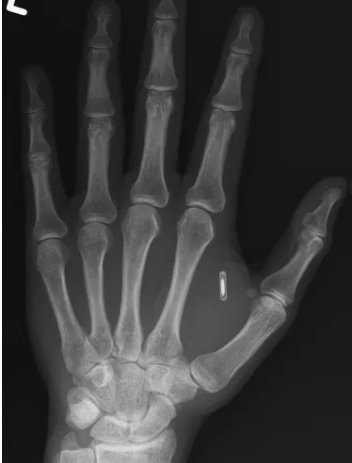

Чіп в руці фокусника